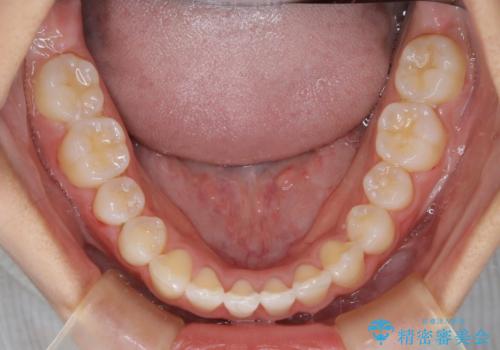

- 前歯の叢生(がたつき)を主訴に来院された患者様です。以前マウスピース矯正をされていたそうでしたが、自身での継続が難しいことなどを理由に、ワイヤー矯正にて改めて矯正治療を希望されました。非抜歯にて治療を計画し治療を行いました。

歯の動きが良く、スムーズに治療を終了しました。一般的にワイヤー矯正はブラッシングが難しいのですが、毎回一生懸命セルフケアをされていたのが印象的です。治療においては、歯の衛生状態も一緒にチェック致します。